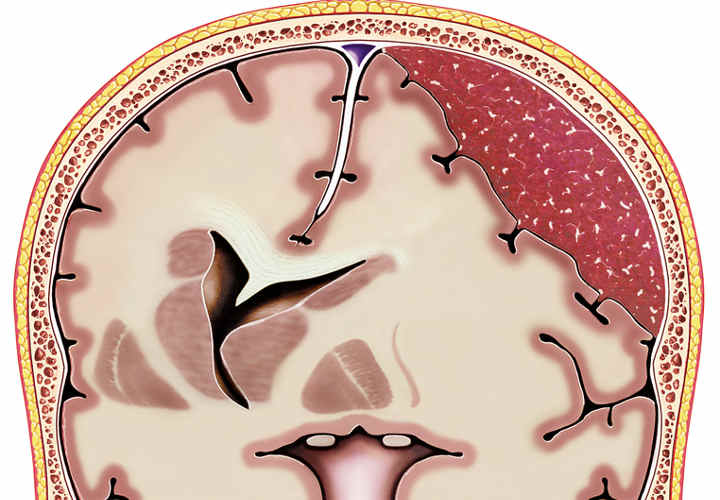

Aneurismas

Un aneurisma es un ensanchamiento de las paredes de una arteria. Si se llega a romper uno, puede provocar una hemorragia peligrosa e incluso la muerte. Las mujeres son más propensas que los hombres a sufrir aneurismas cerebrales, en una proporción de 3 a 2.

- Un aneurisma es una dilatación de una arteria que se ocasiona por el debilitamiento de la pared vascular. Las arterias son vasos sanguíneos que transportan sangre oxigenada desde el corazón hacia otras partes del cuerpo.

- Cuando crece un aneurisma, se puede romper y provoca una hemorragia peligrosa.

- La mayoría de los aneurismas ocurre en la aorta, la arteria principal que sale del corazón y pasa por el pecho y el abdomen. También pueden ocurrir en las arterias del cerebro, el corazón y otras partes del cuerpo. Si un aneurisma cerebral se rompe, produce un derrame.

- El aneurisma saliente puede poner presión sobre un nervio o tejido cerebral circundante.

- También pueden perder o romperse, derramando sangre en el tejido circundante (llamado hemorragia).